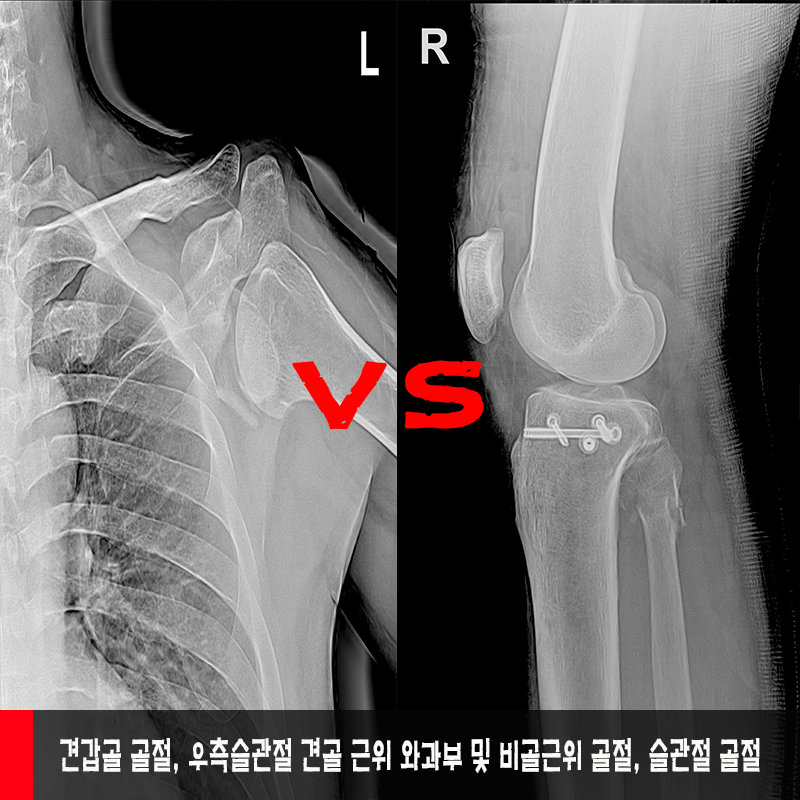

견갑골 골절, 우측슬관절 견골 근위

와부부 및 비골근위 골절, 슬관절 골절

견갑골 골절, 우측슬관절 견골

후유장해진단에 대하여